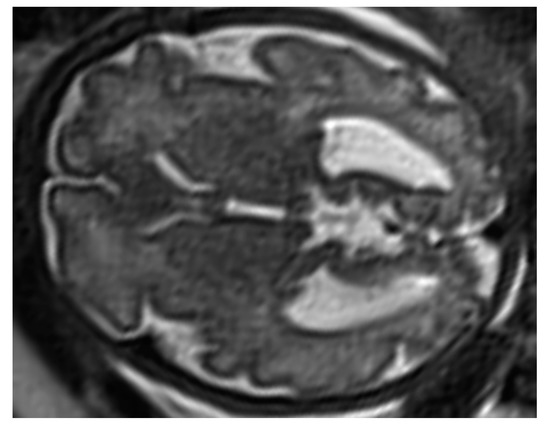

3.2.1. Ventriculomegaly

3.2.2. Central Line Defects

Agenesis of Corpus Callosum

Holoprosencephaly

Agenesis of the Cavum Septum Pellucidum